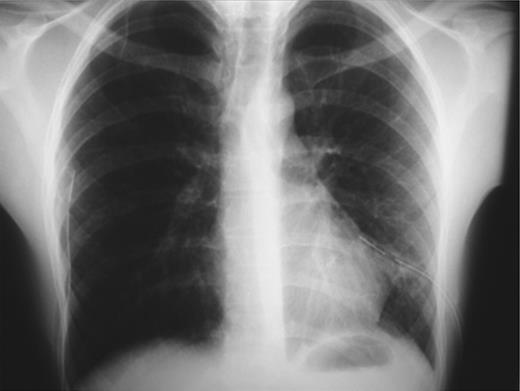

An otherwise-healthy, non-smoker, 20-year-old, overweight (BMI 29.8 kg/m2) Greek male patient was presented to the emergency department complaining of low-intensity chest pain and breathlessness of progressive worsening over the preceding 7 days. On admission, physical examination revealed diminished breath sounds on both sides. Blood pressure was 125/70 mmHg, heart rate 100 beats/min, SaO2 97% on air and axillary temperature 36.8°C. Laboratory tests were normal. Initial plain chest X-ray demonstrated bilateral pneumothoraces (more prominent on the left side) and no deviation of the trachea (Fig. 1).

Plain chest X-rays on admission revealing bilateral pneumothorax.